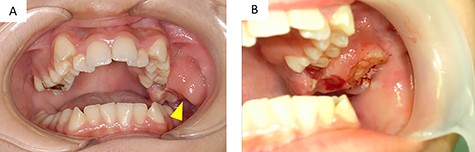

A 12-year-old girl presented to our clinic with a chief complaint of trismus. A few months ago, she noticed a bulge in the left maxillary gingiva and trismus. There was no spontaneous pain, but pressure pain was felt. She was afebrile, had no history of trauma or medications. During her first medical examination at our clinic, she was 164 cm tall, weighed 54 kg. Extraoral examination revealed a slight bulge in the left cheek with countenance, right and left asymmetry and trismus. The range of mouth opening was 18 mm, and there were no swollen lymph nodes that I could feel in the neck. Intraoral findings revealed a neoplastic lesion extending from the left maxillary first molar to the maxillary tuberosity (Fig. 1A). It interfered with the occlusion on that side.

(A) intraoral findings of a suspected neoplastic lesion extending from the maxillary tuberosity to the left maxillary first molar at the time of initial examination (arrowhead); (B) intraoral findings at the time of biopsy; the sectioned surface was milky-white with enhancement characteristics